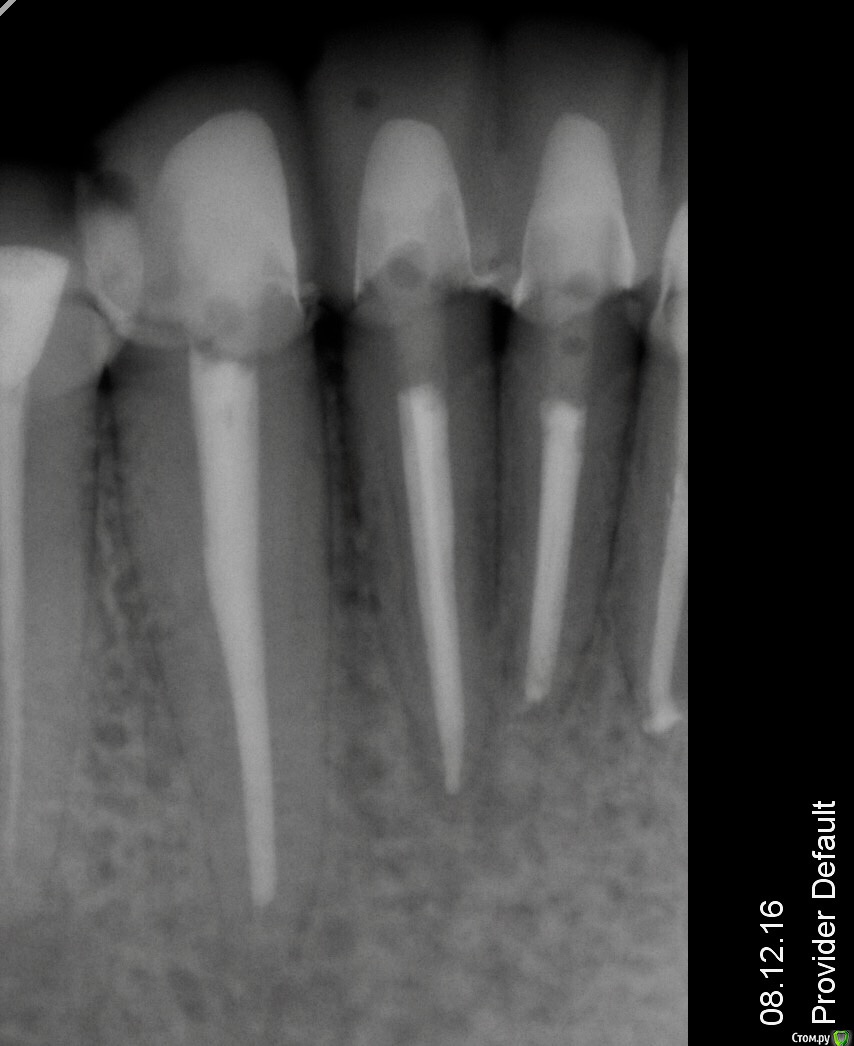

Гарриевич Опубликовано 9 декабря, 2016 Поделиться Опубликовано 9 декабря, 2016 вот "киста"А ниже снимок через 1,5 года, нет "киста". Лечите, если есть мотивация 1 Ссылка на комментарий

Гарриевич Опубликовано 13 декабря, 2016 Поделиться Опубликовано 13 декабря, 2016 (изменено) Просто для понимания и для других пациентов, которые может буду читать вашу тему. Вот тут "киста" размером в 2-3 см и это НЕ показание к удалению. Сейчас пациент проходит терапевтическое лечение, все симптомы исчезли. Размер поражения абсолютно не влияет на исход лечения Изменено 13 декабря, 2016 пользователем Гарриевич 5 Ссылка на комментарий